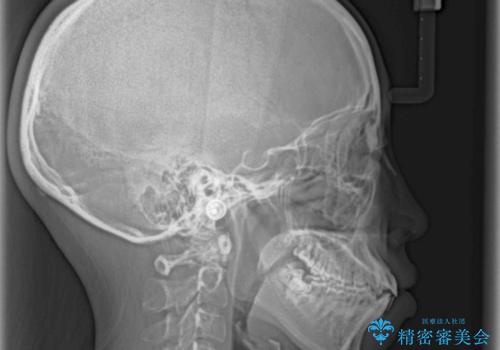

- 前歯が突出しているために口が閉じられないとのことで来院された患者様です。

上下ともに顎が小さく、歯列が前方に突き出していたため、上下左右の第一小臼歯4本を抜歯し、口元の突出感を改善していくこととしました。